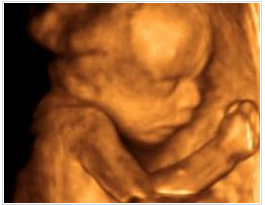

醫(yī)生一邊給醫(yī)生助理報(bào)數(shù)據(jù),一邊耐心的為我講解,哪里是寶寶的手啊腳啊,之后我們又聽到了臍血流和胎心音,醫(yī)生說寶寶的身體很健康,一切都正常,我這才放心下來。整個(gè)四維彩超檢查過程大約持續(xù)1個(gè)小時(shí),可我仍覺得意猶未盡,期間還把寶寶的萌照拍了下來,是不是很可愛呢?

做四維彩超所看到的胎兒在宮內(nèi)的情況